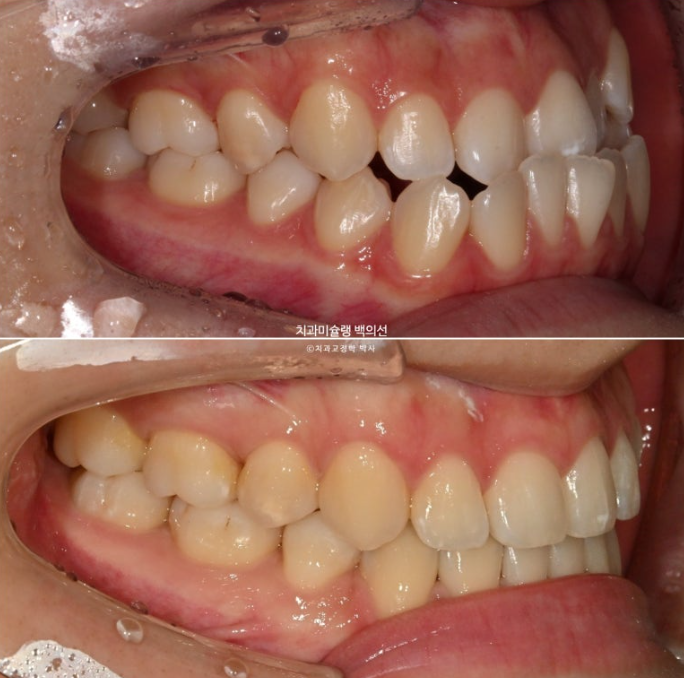

23.11~25.10

앞니가 거꾸로 물리는 반대교합이 해결되었습니다.

아랫입술이 뒤로 들어가며 입매가 조화로워 졌습니다.

정밀한 후방이동량 조절의 결과

발치교정임에도 불구하고 아래턱끝이 부각되어 보이지 않습니다.

이에 따른 아랫입술의 후방이동이 눈에 띕니다.

결과가 아주 좋습니다.